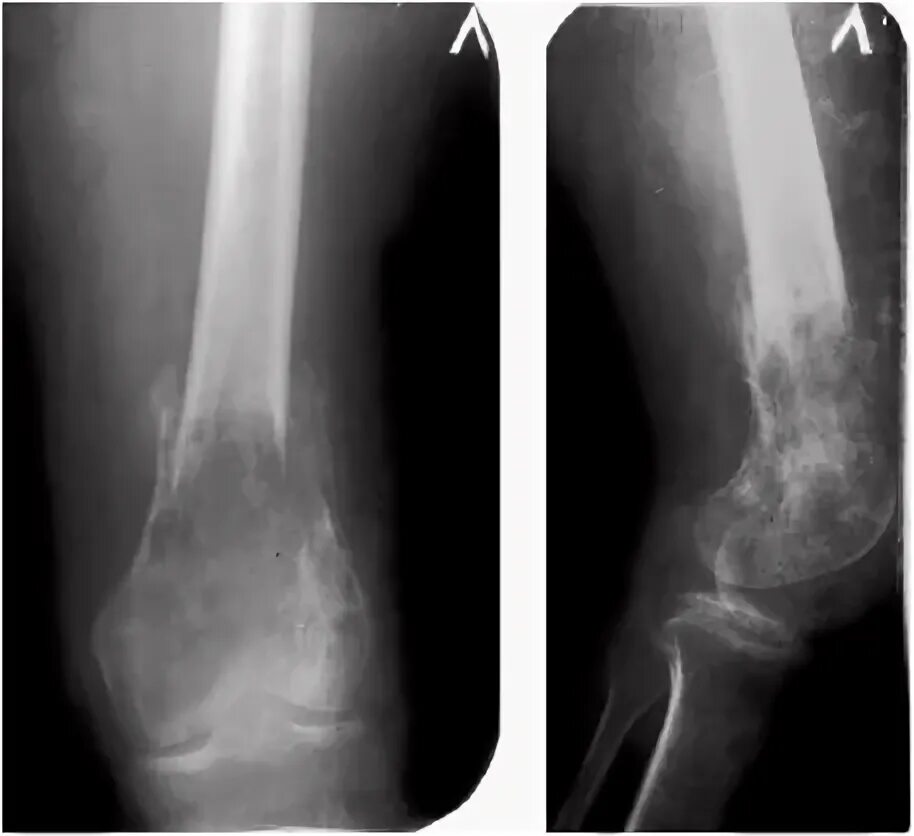

Патологический перелом бедра